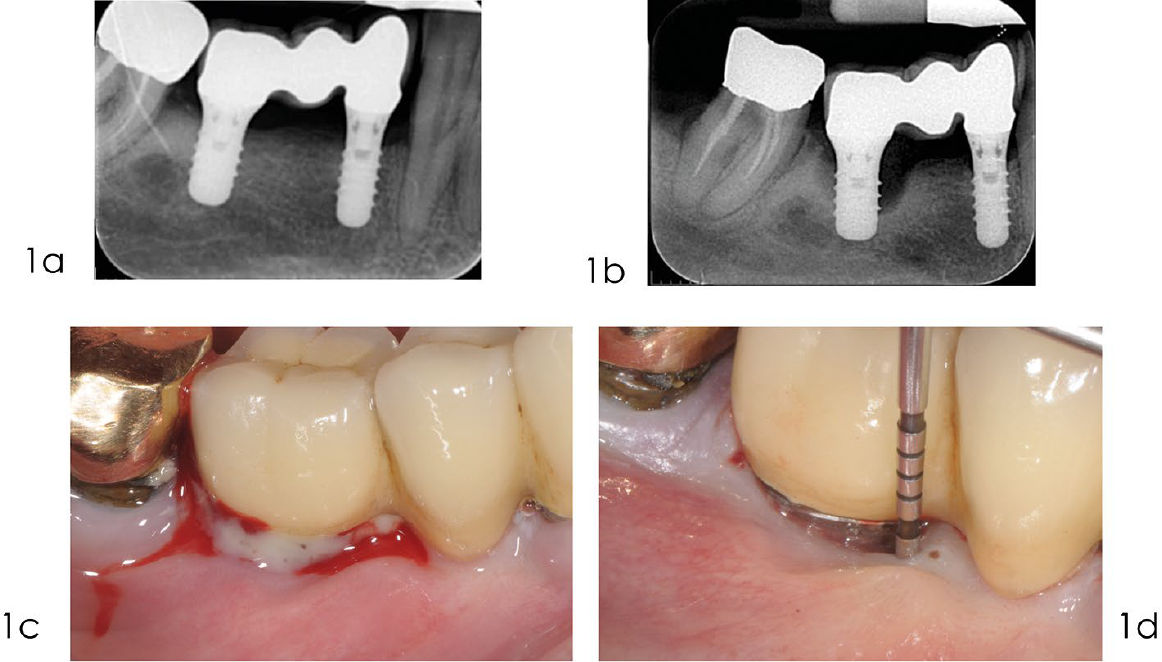

Фото 1. Реконструктивное лечение периимплантита: диагностика

a) Рентгенограмма, выполненная в сентябре 2010 года, через три года после установки протеза, показывает оптимальный уровень кости вокруг имплантата. b) Рентгенограмма, выполненная в декабре 2014 года, демонстрирует выраженную краевую убыль кости в области имплантата 4.6. c) Кровоточивость при лёгком зондировании и/ или наличие гноя — основные клинические признаки мукозита и периимплантита. d) Участки с периимплантитом характеризуются клиническими признаками воспаления, увеличенной глубиной зондирования, а также рентгенологической убылью кости по сравнению с предыдущими обследованиями. Существует определённая связь между периимплантитом и отсутствием кератинизированной слизистой